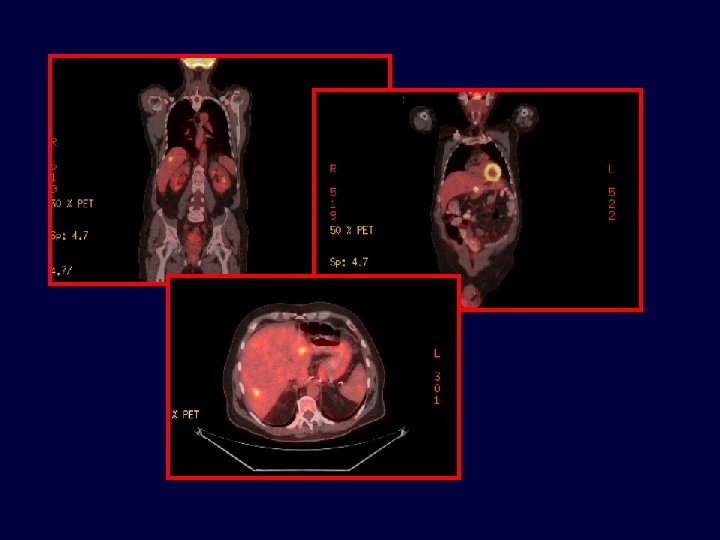

Cáncer de colon metastásico resecable Sospecha TAC de TAP PET-CT